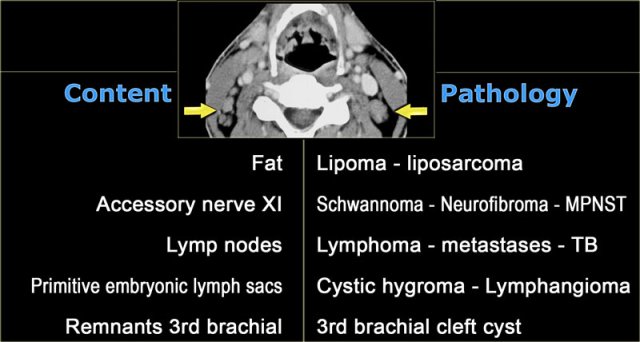

Posterior cervical space

On the left a table with the normal contents of the posterior cervical space and subsequent pathology.

MPNST is short for malignant peripheral nerve sheath tumor, which is the proper name for a malignant schwannoma.